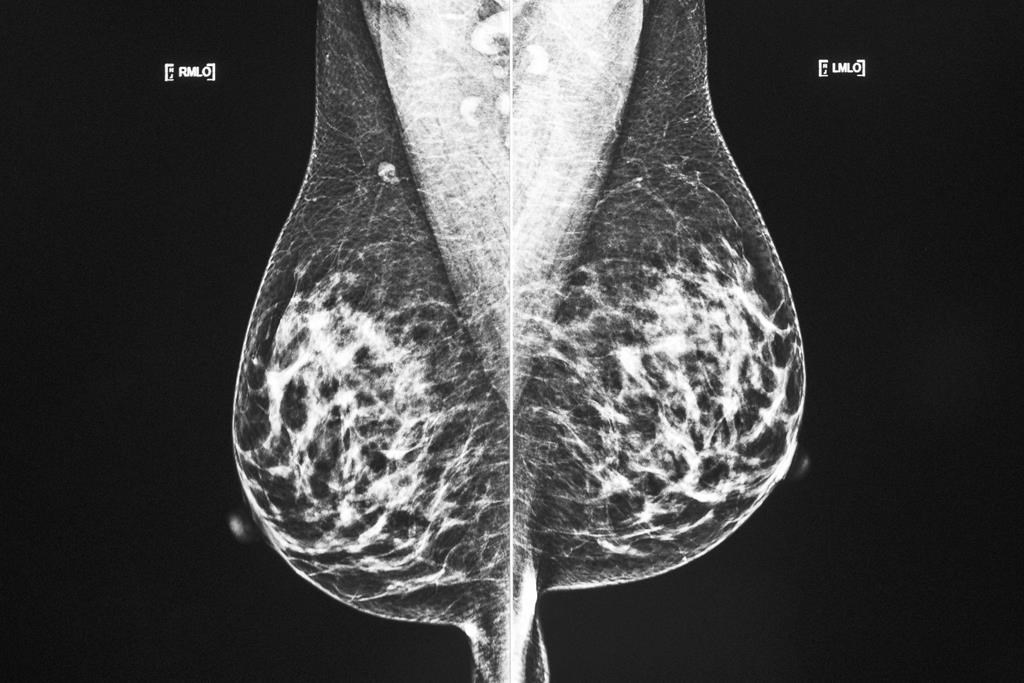

Une étude détaille l'association entre l'obésité et le cancer du sein

MONTRÉAL — L'obésité pourrait augmenter le risque de cancer du sein chez les femmes dont le risque est déjà plus élevé parce qu'elles sont porteuses des mutations génétiques BRCA1 et BRCA2, prévient une étude à laquelle a participé un chercheur montréalais.